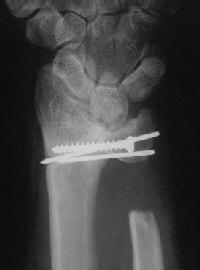

Right side, postop.

Click for larger image